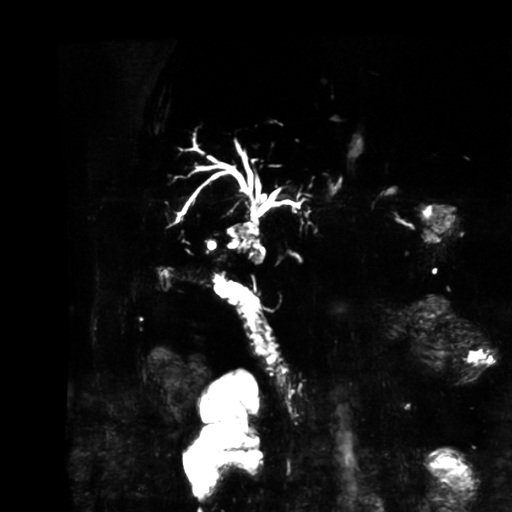

Se observa dilatación de las vías intra hepáticas a expensas de sus ramas hepáticas derecha, anterior y posterior, hepática izquierda y hepática común. El hepático común da la apariencia de estar anastomosado a un asa de intestino, lo que sugiere la posibilidad de una cirugía entero biliar.

No se logra observar el colédoco.

1. Dilatación de vías biliares intrahepáticas

2. Anastomosis entero biliar

3. Colangitis aguda

o Dilatación segmentaria o difusa de los conductos intrahepáticos proximal a la anastomosis.

o Estrechamiento focal o filiforme en el sitio de la unión bilioentérica.